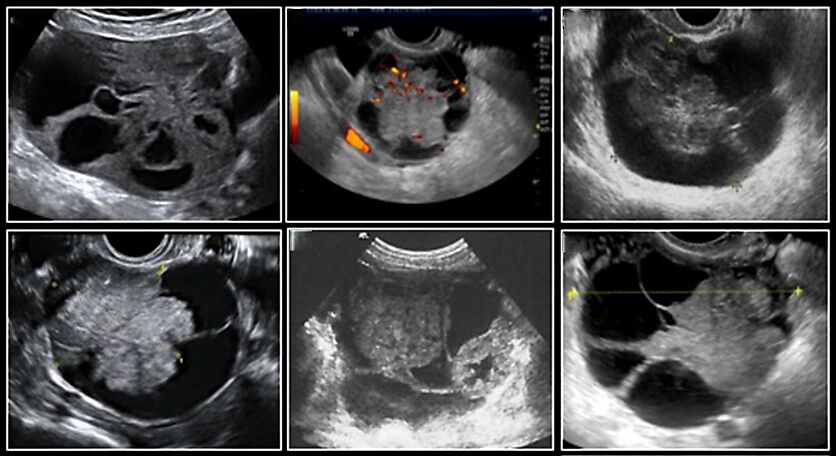

In a retrospective multicenter study including 239 histologically confirmed pure endometrioid carcinomas, the tumors typically appeared on ultrasound as multilocular-solid (48%) with low-level (53%) or ground-glass (16%) cystic fluid, or solid (34%), with a median diameter of 102 mm. On retrospective review by Moro et al., 54.8% of endometrioid cancers developing from endometriosis were described as cysts with papillary projections.17 The most typical (36.3%) ultrasound image of an endometrioid cancer not developing from endometriosis was a cyst with a large central solid component entrapped within locules. This pattern resembles the concentric layers of a cockade, hence the term ‘cockade sign’ (Figure 7).

7

Ultrasound images of endometrioid carcinoma without evidence of tumor developing from endometriosis on histological examination. Carcinomas were described as multilocular-solid masses showing a cockade-like appearance. Adapted from Moro et al.17